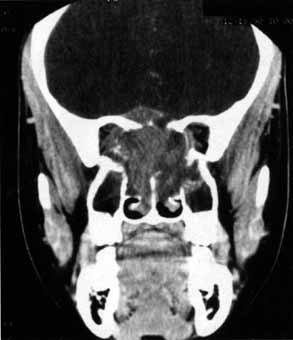

Fig. 19 A. A patient underwent endoscopic exploration of the right ethmoid and maxillary sinus for persistent epistaxis. Postoperatively the patient demonstrates right proptosis, restricted extraocular movements of the right eye, and a dilated right pupil. Instillation of 0.1% pilocarpine resulted in miosis on the right and no change on the left. Computed tomography (CT) shows a vessel clip lateral to the optic nerve (arrow), near the position of the ciliary ganglion. B. Coronal CT scan showing the clip lateral to the optic nerve (arrow).

Anosmia caused by damage of cranial nerve I may be a helpful symptom of ethmoid or sphenoid sinus tumors invading the orbit (Fig. 20).44 Olfactory groove meningiomas and esthesioneuroblastomas may also present with anosmia prior to developing vision loss.45 Trauma that involves the orbit and is associated with anosmia should be considered a basilar skull fracture with potential for cerebrospinal fluid leak until proven otherwise (Fig. 21).

Fig. 20 A 13-year-old child presented with a 2-week history of sinusitis and anosmia. Her visual acuity decreased to to 20/400 1 day prior to admission. Computed tomography shows a large ethmoid tumor extending through the cribriform plate and optic canal. A rhabdomyosarcoma was diagnosed by biopsy.